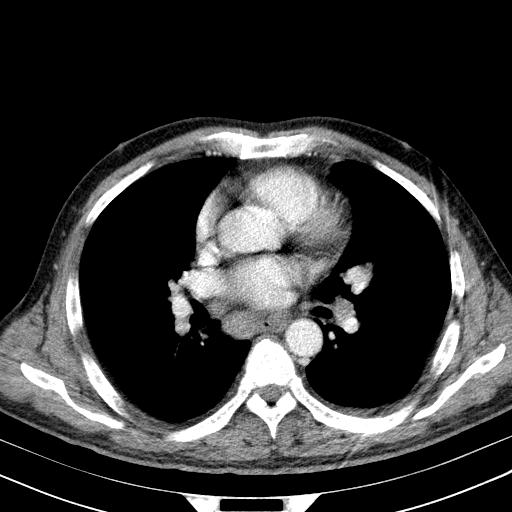

先行ct平扫,纵膈内多发软组织影,ct值约为36hu,以下为增强扫描和腹部平扫。

经典?纵膈多发肿大淋巴结。腹膜后未见异常。

还见胃窦壁增厚!转移亦有可能!

1)考虑淋巴瘤。2)双侧少量胸腔积液。